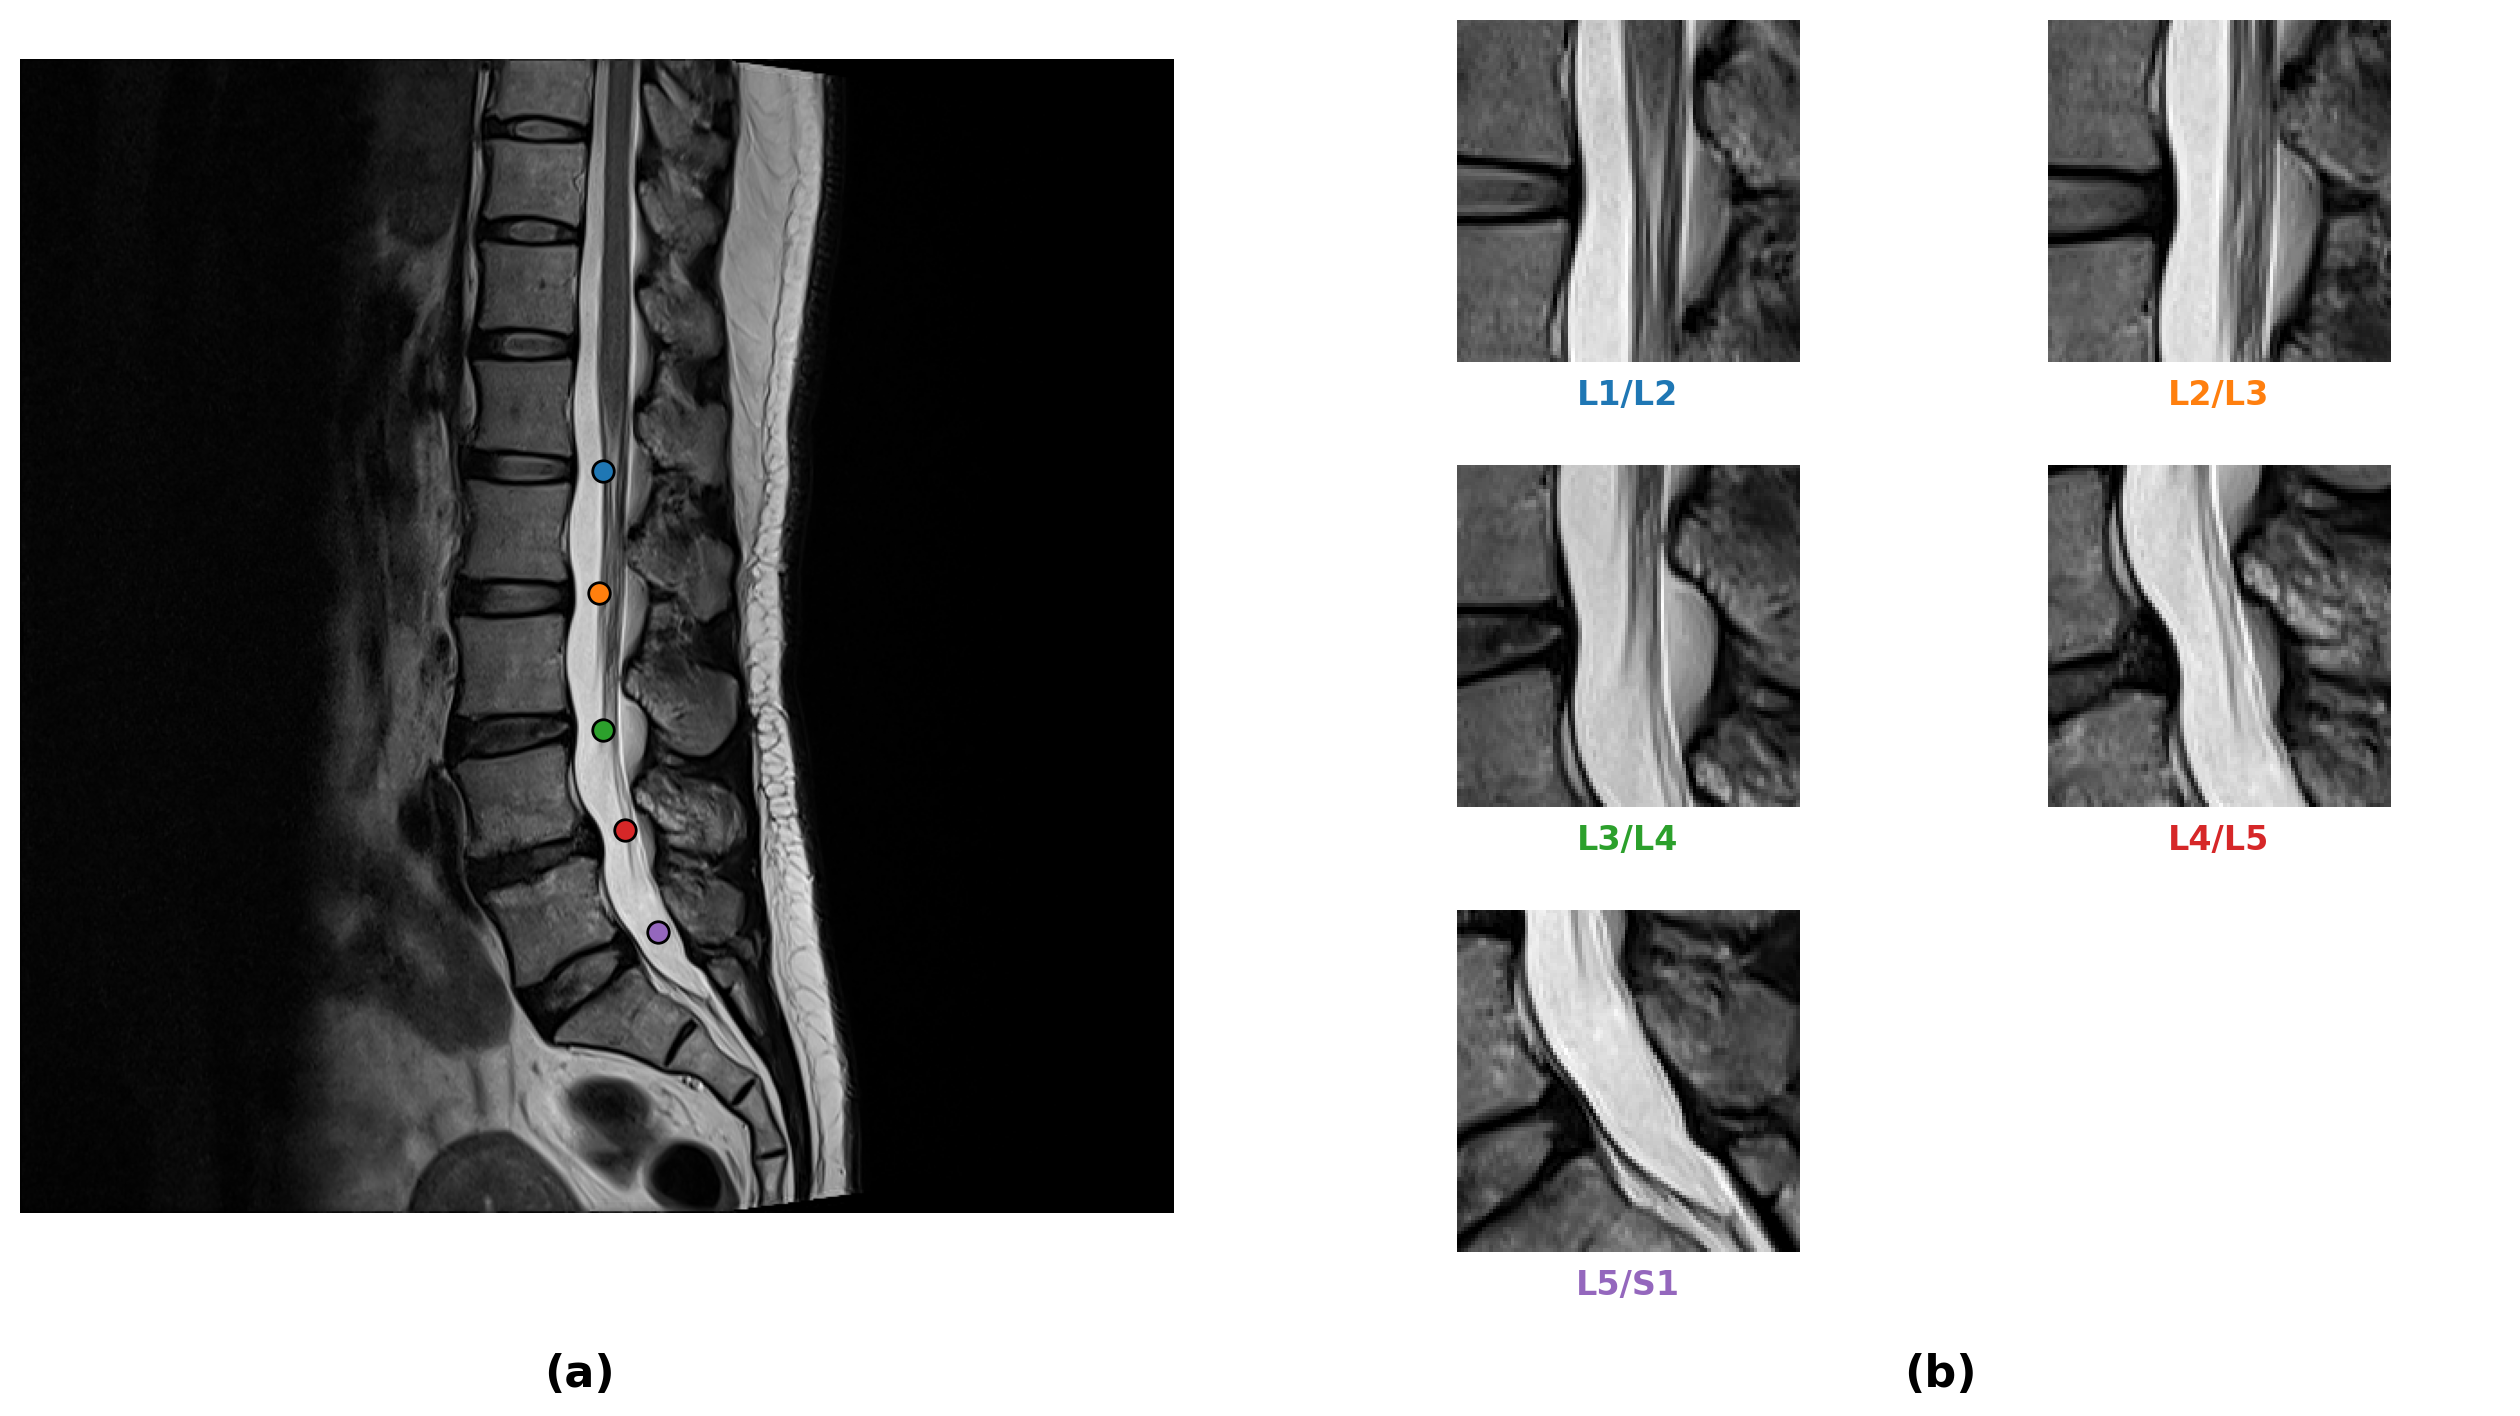

Refer to caption

Figure 4: Visualization of model performance on a representative patient series (L1/L2, L2/L3). Each row corresponds to a vertebral level. Left: Original MRI with Ground Truth (green circle). Right: Model prediction (red cross) versus Ground Truth.

The model was trained for 40 epochs, achieving its best performance at epoch 31, with an overall loss of 0.0016 and a RMSE of 10.18 pixels on the test dataset. These results demonstrate that the proposed ROI network can reliably predict anatomical coordinates of intervertebral discs with high precision and stable quantitative performance. This serves as an effective auxiliary tool to support our classification task.